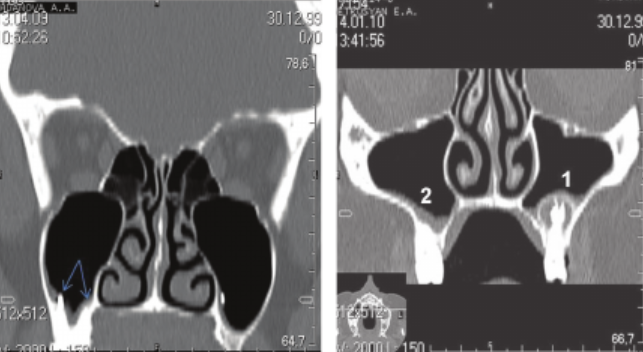

При хроническом течении трихомонадной инфекции происходят изменения слизистых покровов шейки матки и влагалища – возникают точечные покраснения эпителия, которые представляют собой маленькие кровоизлияния в тканях плоского эпителия.

Поэтому при осмотре окраска шейки матки напоминает клубнику (точечный кольпит), что называют «признаком клубники».